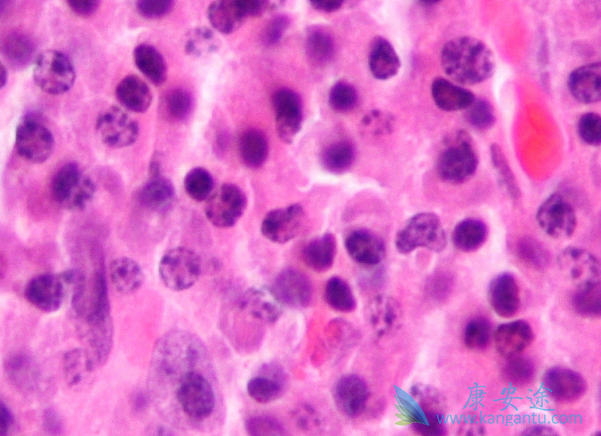

骨髓瘤,是一种恶性肿瘤,是长在骨髓中的一种恶性肿瘤。由于恶性浆细胞瘤有部分长在骨髓里,有一部分是在骨髓外,一半患者在抽骨髓时会发现,因此骨髓瘤也是一种恶性浆细胞瘤。那临床上骨髓瘤症状表现有那些呢?由于骨髓瘤占领了骨髓造血空间,所以60%的患者会出现贫血症状。还有一部分患者会出现不同程度的骨痛。